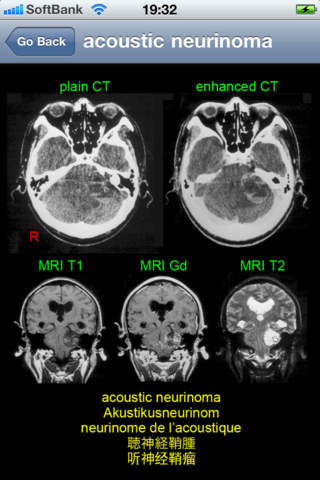

This application is developed to study neuroradiology in English, German, French, Japanese, and Chinese for medical students and professionals such as physicians and nurses. It consists of 26 diagnosis: acoustic neurinoma, acute epidural hematoma, ADEM, aneurysm, arachnoid cyst, arteriovenous malformation, astrocytoma, cerebellar atrophy, cerebral embolism, cerebral hemorrhage, cerebral infarction new and old, cervical disc herniation, chronic subdural hematoma, colon carcinoma metastasis, depressed skull fracture, glioblastoma multiforme, hemorrhagic infarction, meningioma, multiple sclerosis, OPLL, osteoma, pineal cyst, pontine hemorrhage, putaminal hemorrhage, subarachnoid hemorrhage, and syringomyelia.